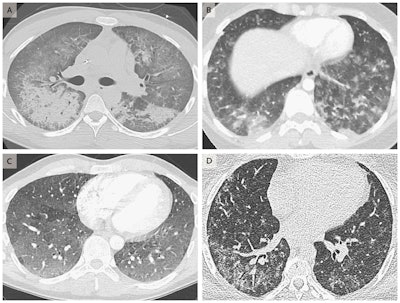

The second study, led by Dr. Travis Henry from the University of California, San Francisco, reported 19 cases in California and Wisconsin that met the criteria for vaping-associated lung injury. They identified several imaging patterns that appeared to correlate with pathology caused by vaping, including signs on CT scans indicating acute eosinophilic pneumonia, diffuse alveolar damage, organizing pneumonia, and lipoid pneumonia.

First, Dr. Sean Maddock and colleagues from the University of Utah Health identified a cluster of six cases in the state that paralleled the findings reported by Layden and colleagues. The most severe case involved a previously healthy 21-year-old man whose CT scans revealed diffuse consolidative opacities and was found to have acute respiratory distress syndrome. The symptoms appeared some time after he began to daily vape nicotine and THC, and the condition improved after several days of oxygen treatment and vaping cessation.

The patients presented with a combination of respiratory, gastrointestinal, and constitutional symptoms, the most common of which included shortness of breath (87%), nausea (70%), and vomiting (66%). All the CT scans acquired turned out to have abnormal findings.